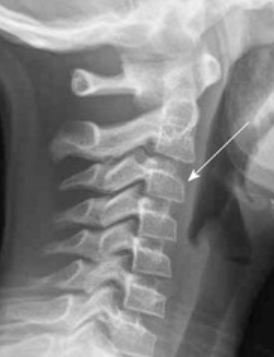

2. Pseudosubluxation of C2

Physiological anterior displacement of C2 on C3 is commonly seen in children, usually <7 years of age, less commonly in older children. It is most commonly seen at C2 on C3, but may less often be seen at C3 on C4. This finding is more pronounced in flexion and can present confusion in the presence of traumatic cervical injury .2 Utilization of Swischuk’s line is useful in differentiating pathological anterior cervical spine displacement from physiological displacement. This line is drawn from the anterior aspect of posterior arch of C1 to anterior aspect of posterior arch of C3 3 and should measure less than 2-mm. A measurement of greater than 2-mm indicates true subluxation. It is important to note that this line should only be used in the absence of other signs of instability and in the absence of prevertebral soft tissue swelling.

Figure 3: a) Pseudosubluxation in a 5-year-old. b) Zoomed in view to demonstrate Swischuk’s line. Case courtesy of Radiopaedia.